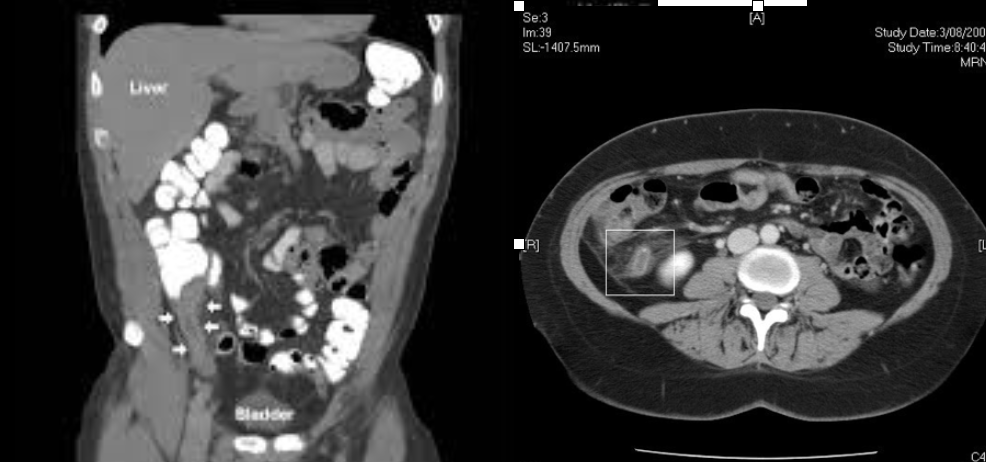

transverse

Which CT view?

coronal

Which CT view?

Abdominal aortic aneurysm (AAA)

CTA Abdomen/Pelvis IV contrast

Trauma: Liver

CTA Abdomen/Pelvis IV contrast

Trauma: Spleen

CTA Abdomen/Pelvis IV contrast